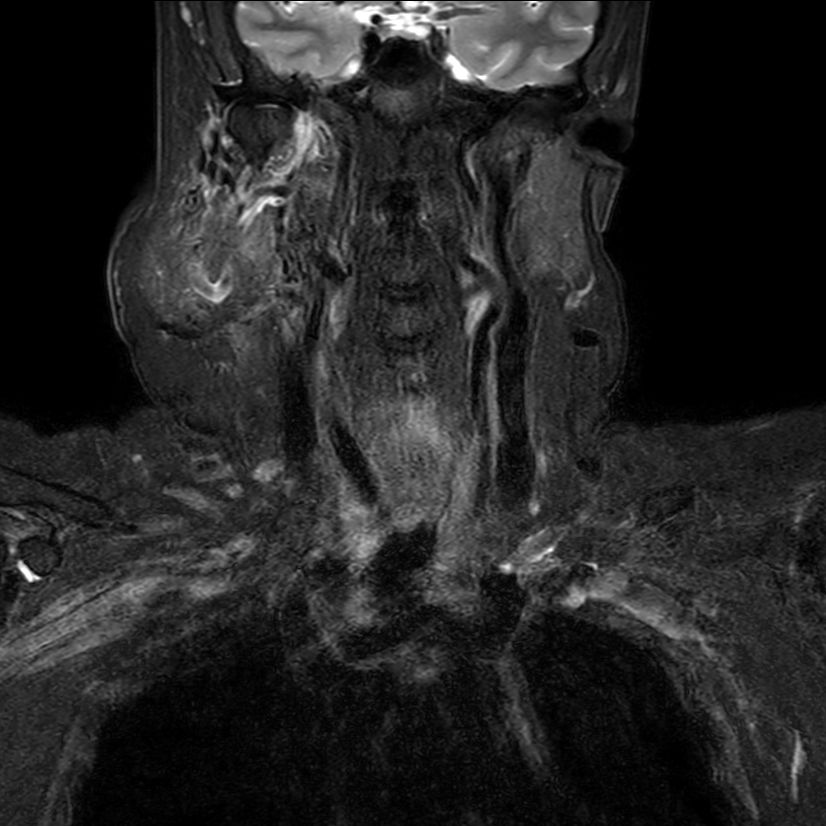

STIR MultiVane XD